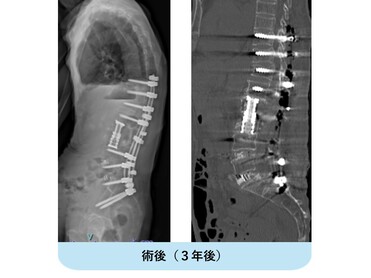

変性後側弯症で正面・側面ともに体幹バランスが破綻しています。まず腰椎側方進入前方固定術を行い、ある程度の矯正、土台を形成。1週間後に胸腰仙椎後方矯正固定術を行いました。正面・側面ともにバランスが良好に維持され、難治性の腰痛が改善しました。

典型的な変性後側弯症、成人脊柱変形の症例です。正面、側面いずれもバランスが破綻していて、立位持続・歩行が困難な状態です。

腰椎側方経路椎体間固定術と後方矯正固定術を2回に分けて行い、正面・側面ともに生理的なshapeが獲得されています。重要なことは、近年この生理的なshapeを取り戻すことが腰痛・歩行障害など患者さんの愁訴の改善に直結することが分かっていることです。